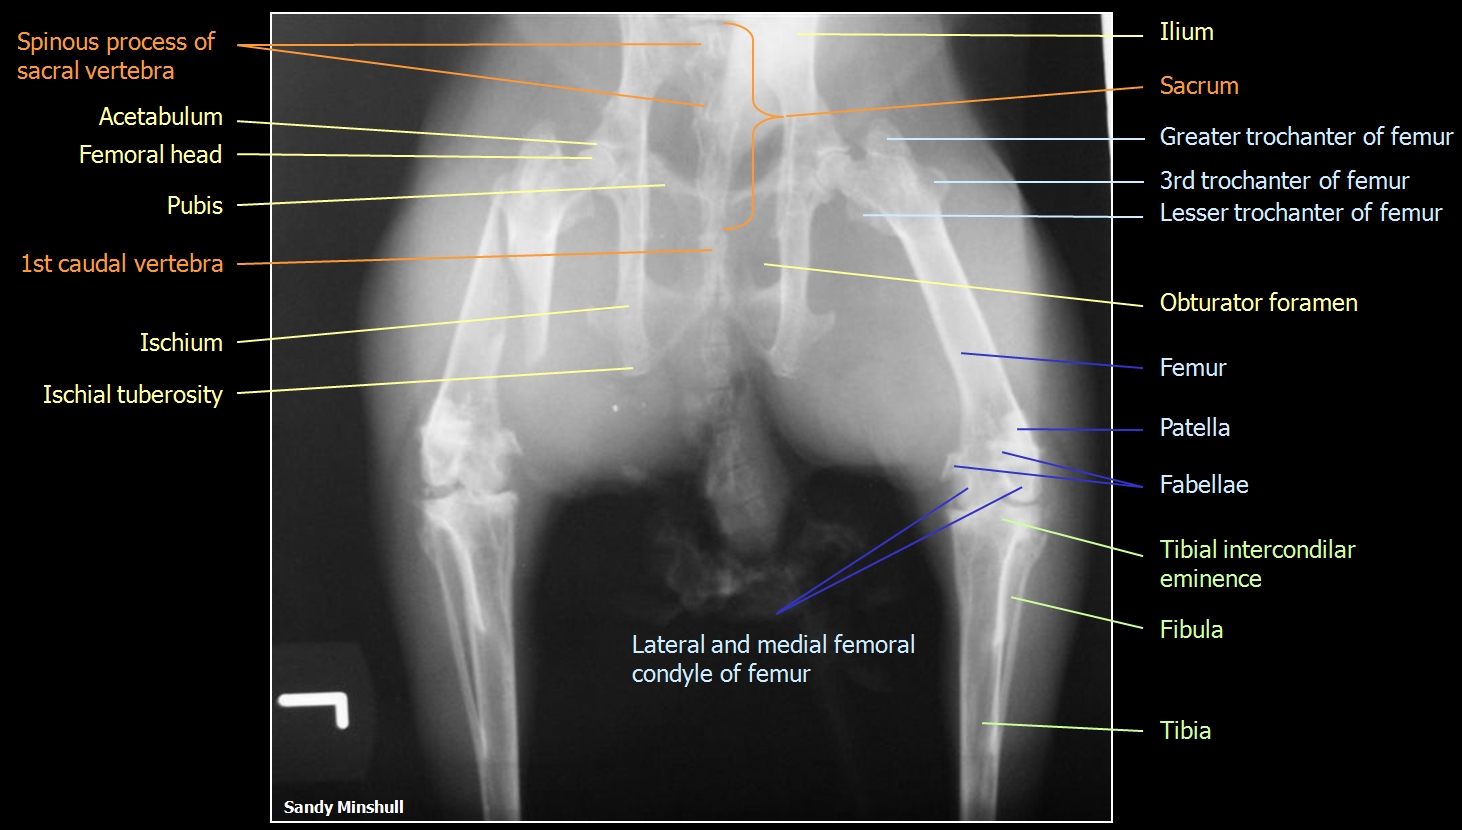

Ventro-dorsal view of the rabbit hip region

Sandy Minshull |